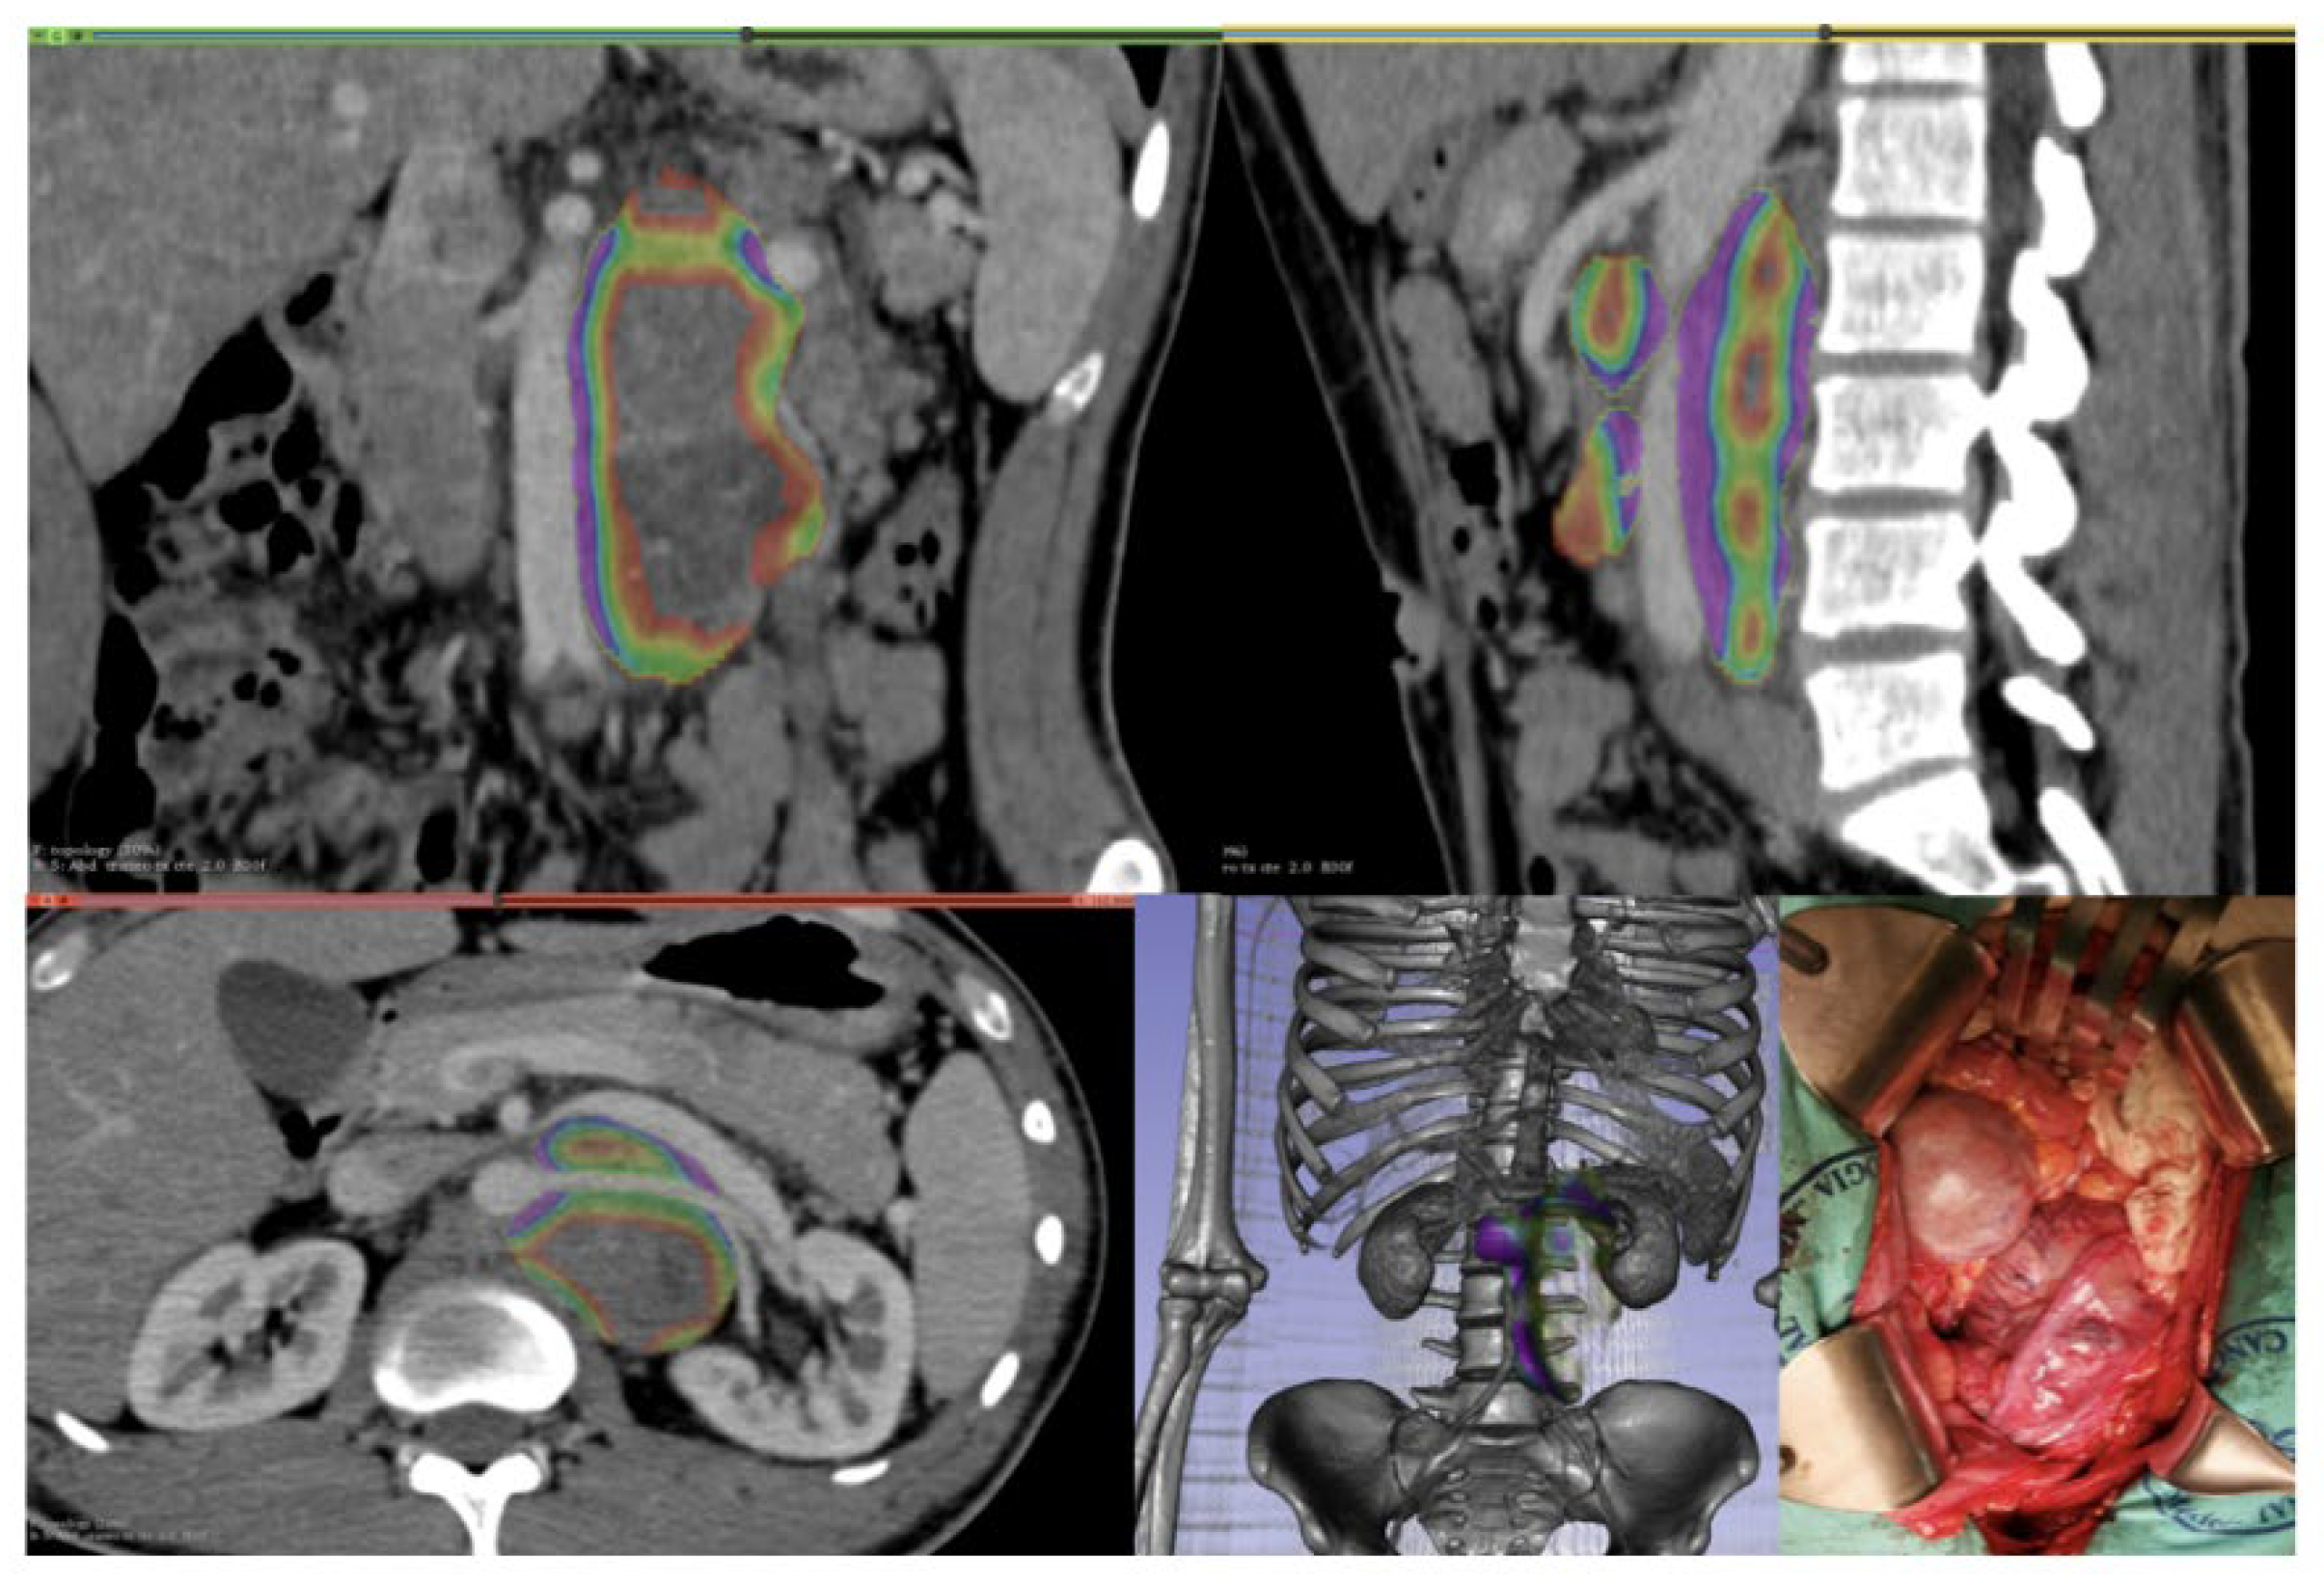

From www.mdpi.com

J. Imaging Free FullText CT Rendering and Radiomic Analysis in Testicular Cancer And Lymph Nodes The clots often occur in. Classical seminoma tends to be diagnosed at an early stage. In a 2023 case study, researchers reported a case of a classical seminoma that spread to a man’s kidney. Here, we review the role of traditional imaging modalities in detecting malignant lymph nodes in patients diagnosed. Alongside high tumor marker levels, stage 3 testicular cancer. Testicular Cancer And Lymph Nodes.